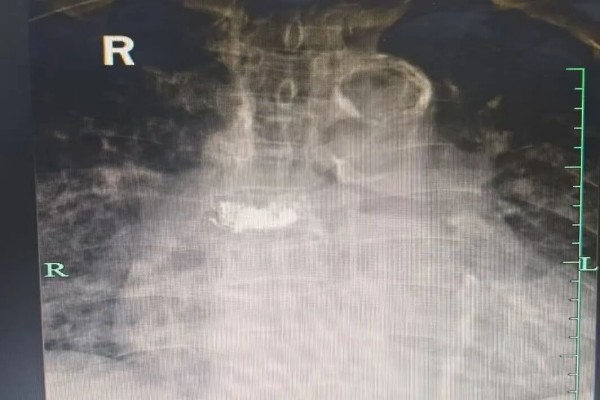

整个手术过程顺利,手术全程仅耗时约30分钟,出血量极微,骨水泥弥散良好且无渗漏,术后安返病房。在严密的监护下,邬大爷生命体征平稳,未出现任何并发症。

术后影像

术前,邬大爷因剧烈疼痛只能坐轮椅,无法站立和行走。而术后他能独自站立并拄拐行走,状态良好,脸上洋溢着久违的笑容。